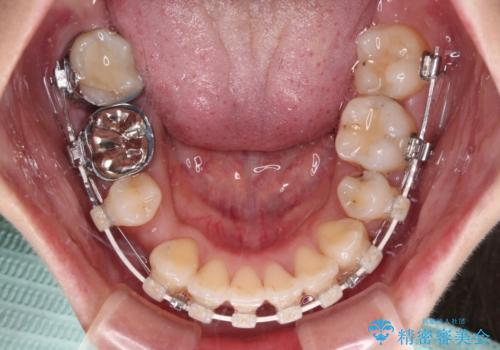

- 口元の閉じにくさを気にして来院された患者様です。

上下ともに歯列が前方に突出していたため、上下左右の第一小臼歯4本を抜去し、ワイヤー装置による矯正治療を行うこととしました。

舌の突出癖による影響もあったため、舌のトレーニングを並行して実施しました。

左下奥歯にむし歯が認められるため、矯正治療後にセラミックインレーにて修復治療を行うこととしました。